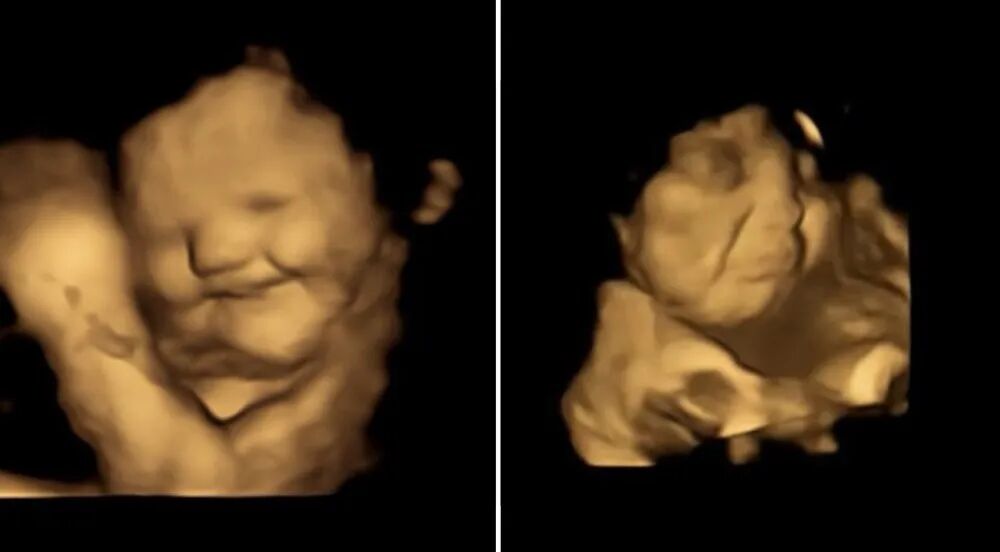

最近英国杜伦大学一项有趣的研究发现,子宫中的胎儿会在妈妈摄入“不好吃”的蔬菜时扮鬼脸。

科学家团队对100名孕妇进行了4D超声扫描,以分析未出生的婴儿对母亲吃不同食物的反应。结果发现,有些喜欢胡萝卜的婴儿,每当妈妈进食胡萝卜就会喜上眉梢,而讨厌羽衣甘蓝的婴儿则会戴上“痛苦面具”。

左:胡萝卜开心;右:羽衣甘蓝痛苦